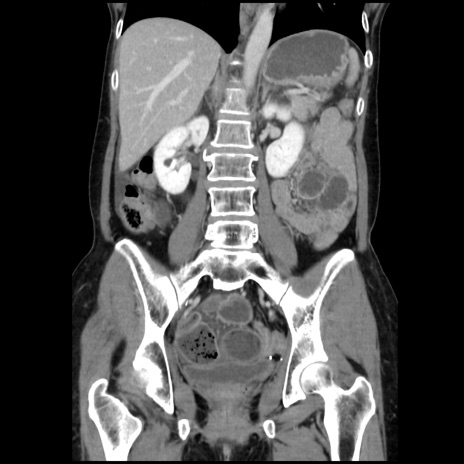

症例32(冠状断像)

【症例】40歳代 女性

【主訴】上腹部痛、嘔気・嘔吐

【現病歴】約9時間前頃から急に上腹部痛、嘔気、嘔吐が出現。改善しないため救急要請。

【既往歴】子宮頚癌(広汎子宮全摘術、放射線療法)、腸閉塞

【身体所見】腹部:平坦、軟、腸雑音亢進、上腹部を中心に腹部全体に圧痛あり。

【データ】WBC 8400、CRP 0.03